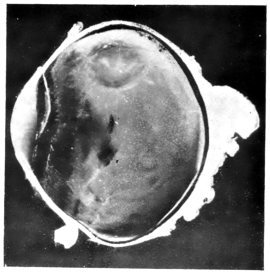

PLATE III.

16.

ABUNDANT EXUDATE INTO VITREOUS CAVITY

curly bracket span

17.

LENS FIRMLY FIXED BY ORGANIZED EXUDATE

18.

LENS FIRMLY FIXED BY ORGANIZED EXUDATE, BUT IN UNUSUAL POSITION

19.

TOTAL DETACHMENT OF RETINA, WITH CYST FORMATION

20.

RECLINED LENS LYING IN FRONT OF THE HYALOID BODY

21.

RECLINED LENS LYING IN FRONT OF THE HYALOID BODYxii